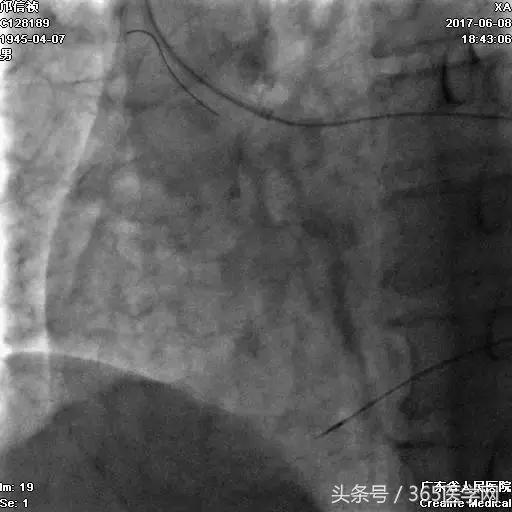

支架术后造影结果